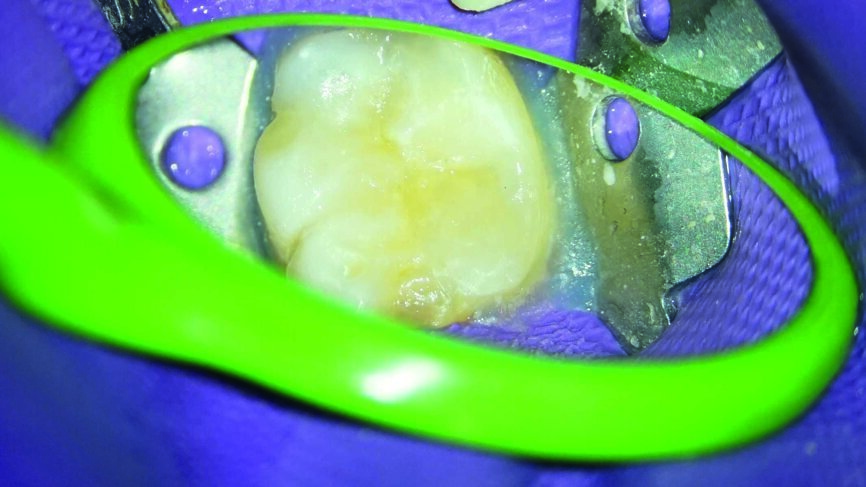

Ein 24-jähriger Patient kam mit vorübergehenden, provozierten Zahnschmerzen an Zahn #19 in die Zahnklinik (Abb. 1). Die Diagnose lautete reversible Pulpitis. Die Zahnfäule wurde unter kompletter Isolation entfernt, wobei es zweimal zur Freilegung der Pulpa mit minimalen Blutungen kam (Abb. 2). Die Blutungen wurden gestoppt, indem 10 Sekunden lang ein mit steriler Salzlösung getränkter Wattebausch auf die Stelle gedrückt wurde. Die Mundhöhle wurde mit 2,5% Natriumhypochlorit desinfiziert (Abb. 3), anschliessend wurde weißes MTA (Produits Dentaires) als Mittel zur unmittelbaren Pulpa-Überkappung eingesetzt (Abb. 4). Um sicherzustellen, dass das MTA korrekt eingesetzt wurde, kam das MAP-System für Dentalmaterialien (Produits Dentaires) zur Anwendung. Mit diesem System kann der Klinikarzt das Material exakt an der Expositionsstelle anbringen. Somit wird eine Verunreinigung der Dentinwände verhindert, die mit der Zeit eine Pigmentierung infolge des verwendeten Materials aufweisen könnten (Abb. 5 und 6). Sobald das MTA auf die Expositionsstellen der Pulpa und die tieferliegenden Teile des Pulpakammerdachs aufgetragen wurde, kam eine lichthärtende Kalziumhydroxidpaste zum Einsatz, um das Material zu schützen (Abb. 7), das Klebeverfahren durchführen und die abschliessende Zahnreparatur in derselben Sitzung vornehmen zu können (Abb. 8 und 9). Sieben Tage nach dem Verfahren war der Patient komplett symptomfrei und der Zahn reagierte normal auf Sensitivitätstests. In solchen klinischen Situationen ist davon auszugehen, dass zwischen sechs und neun Monaten nach dem Verfahren die Bildung von Kalkgewebe unter dem Überkappungsmaterial in Röntgenaufnahmen nachgewiesen werden kann. (7)